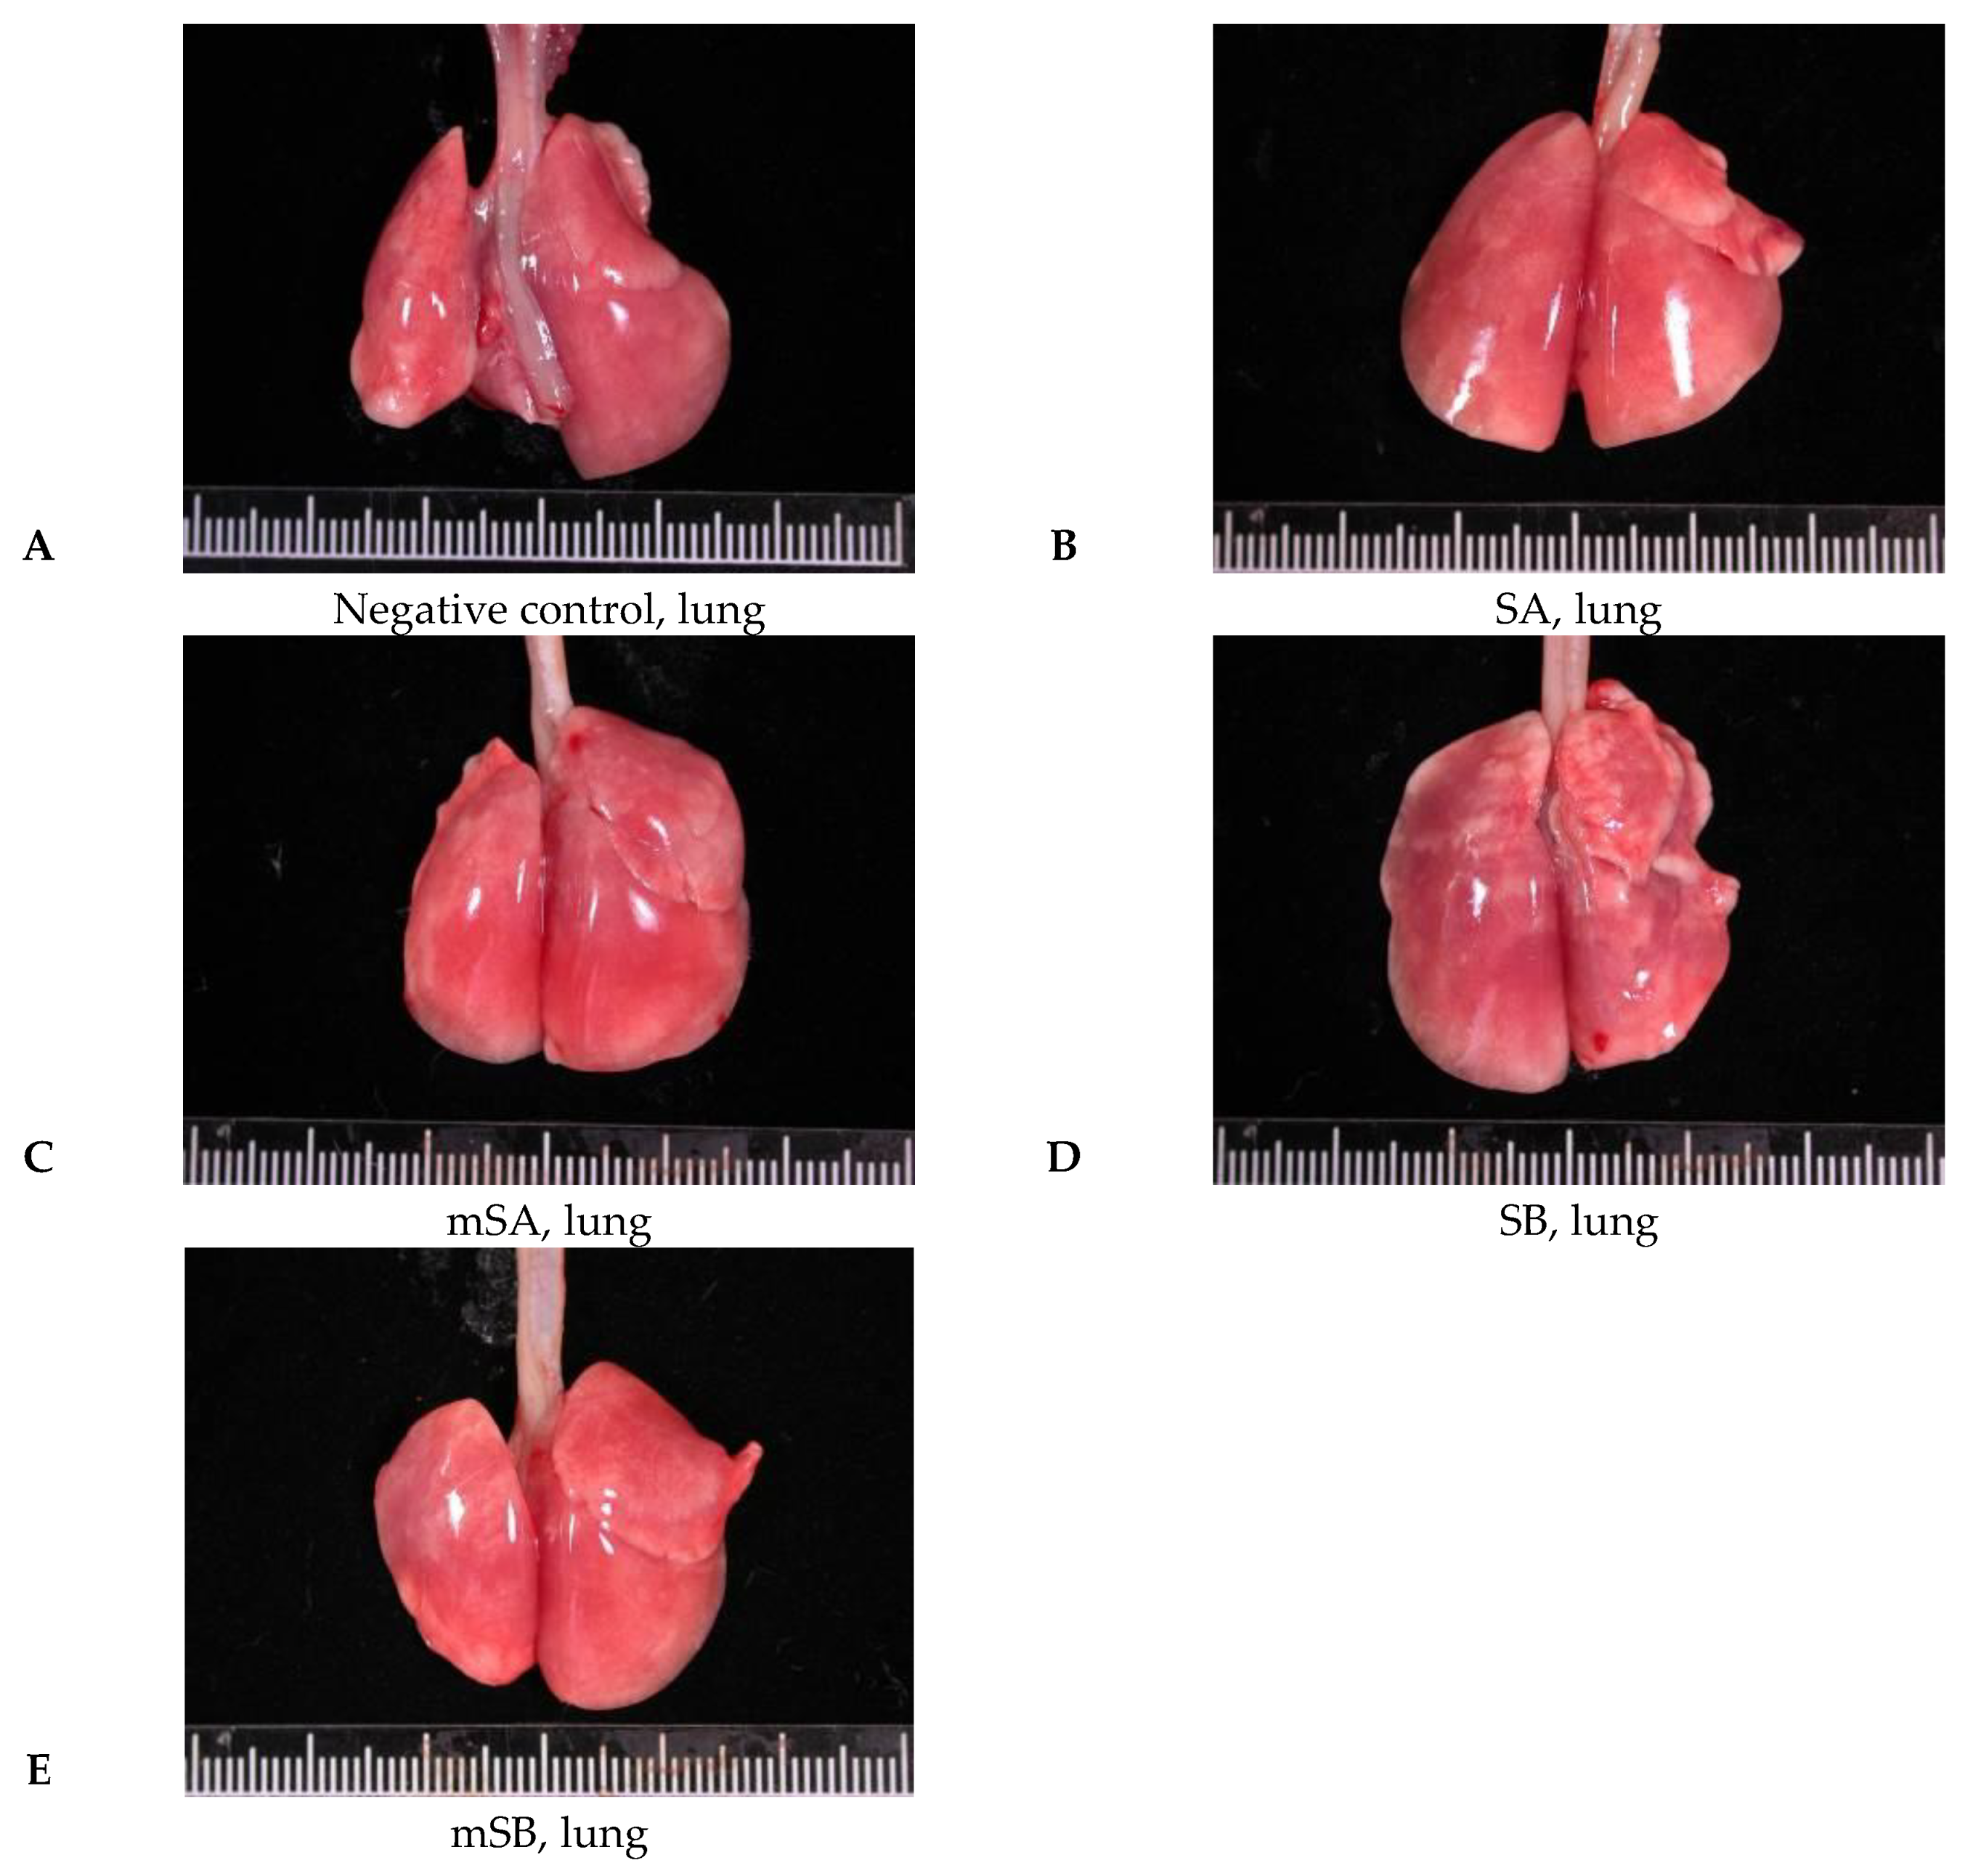

3.5. Acute Pulmonary Toxicity Test (14 D)

| Pathological Incidence | ||||||

| Organ | Lesions | Group | ||||

| NC 1 | SA | mSA | SB | mSB | ||

| Lung | ||||||

| Aggregate of macrophage, alveolar multifocal | - | 4/5 2 | 5/5 | 5/5 | 0/5 | |

| Granulomatous inflammation, alveolar, focal | - | - | - | 5/5 | 0/5 | |

| Pathological Scores | ||||||

| Organ | Lesions | Group | ||||

| NC | SA | mSA | SB | mSB | ||

| Lung, left lobe | ||||||

| Aggregate of macrophage, alveolar multifocal | 0.0 ± 0.0 3,4 | 2.2 ± 1.5 * | 1.6 ± 0.5 * | 2.2 ± 0.4 *,a | 0.0 ± 0.0 a | |

| Granulomatous inflammation, alveolar, focal | 0.0 ± 0.0 | 0.0 ± 0.0 | 0.0 ± 0.0 | 1.6 ± 0.5 *,a | 0.0 ± 0.0 a | |

| Total score 5 | 0.0 ± 0.0 | 2.2 ± 1.5 * | 1.6 ± 0.5 * | 3.8 ± 0.8 *,a | 0.0 ± 0.0 a | |

| Group | M (105) | N (105) | L (105) | E (105) |

|---|---|---|---|---|

| NC 1 | 3.41 ± 0.88 2 | 0.03 ± 0.01 | 0.07 ± 0.05 | 0.00 ± 0.00 |

| SA | 3.94 ± 0.49 | 0.18 ± 0.16 | 0.16 ± 0.08 | 0.01 ± 0.03 |

| mSA | 7.28 ± 4.11 | 0.03 ± 0.03 | 0.19 ± 0.13 | 0.00 ± 0.00 |

| SB | 5.09 ± 2.97 | 0.29 ± 0.24 * | 0.39 ± 0.41 | 0.00 ± 0.00 |

| mSB | 3.97 ± 2.31 | 0.23 ± 0.34 | 0.16 ± 0.07 | 0.00 ± 0.00 |